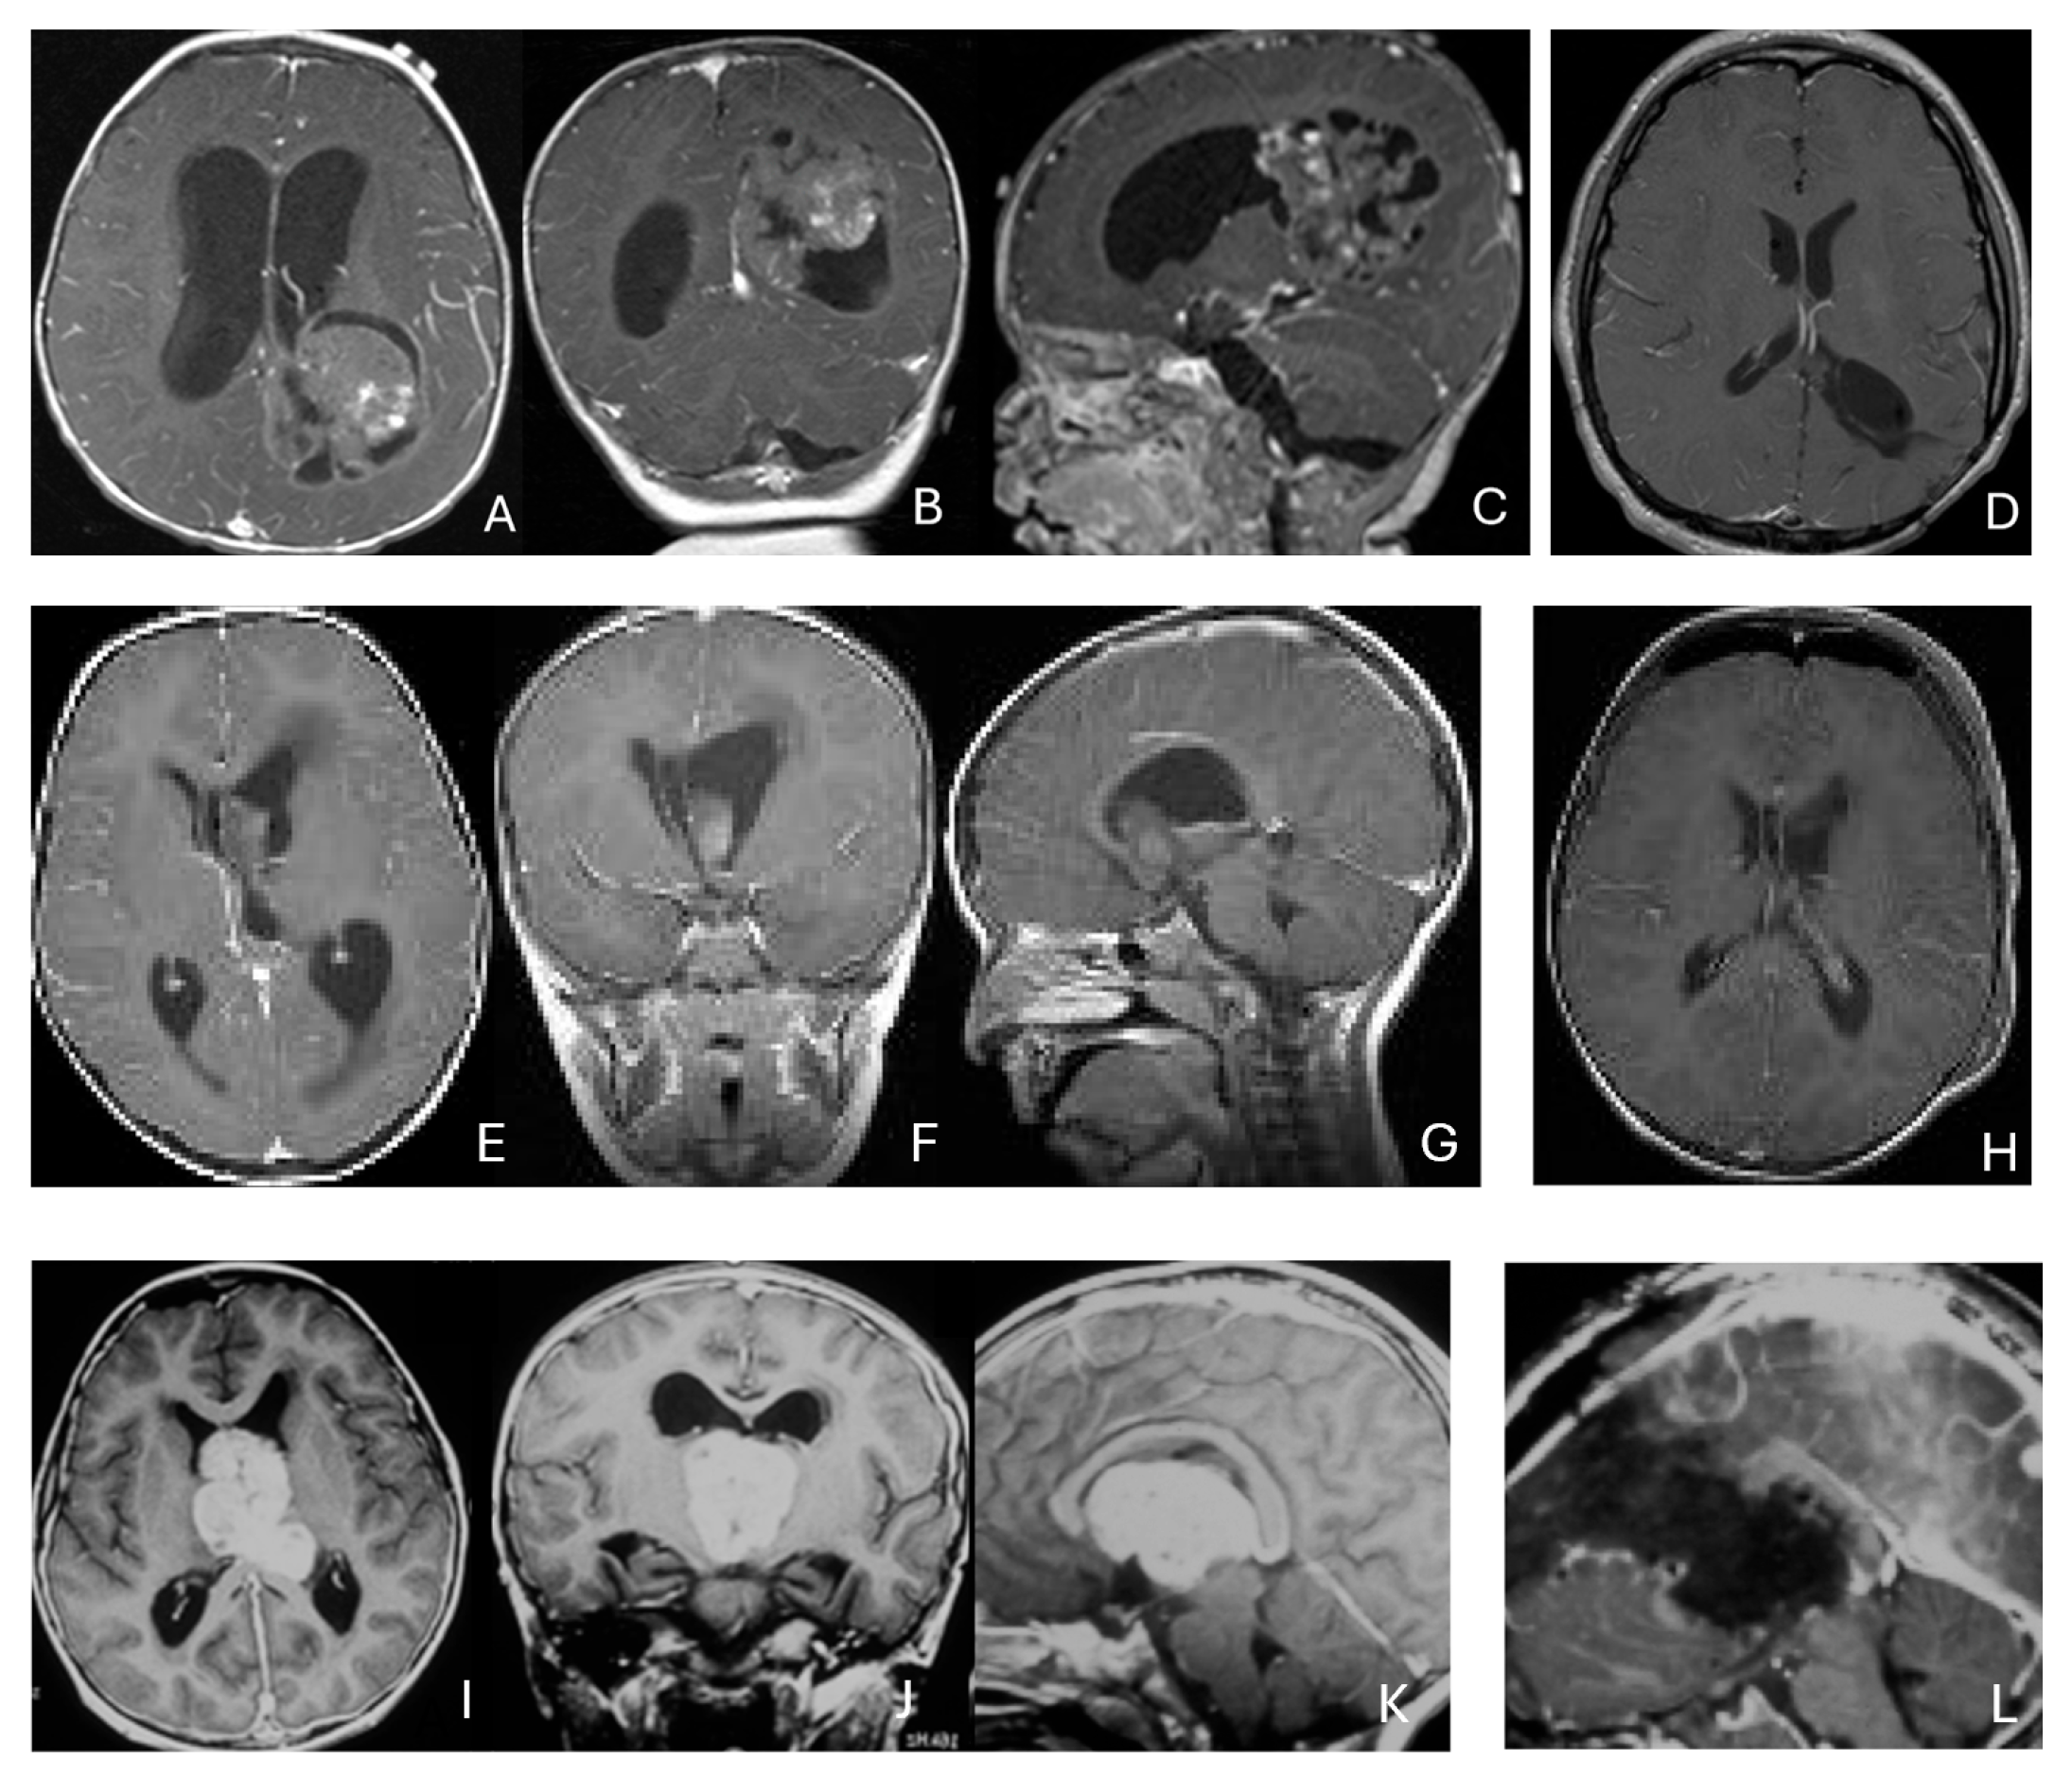

Eight patients had lesions localized to the CPA/CMF region (Figure 9). Among them, two had concurrent bilateral lesions. In one bilateral case, the lesions were asymmetric with questionable evidence of spinal cerebrospinal fluid dissemination, whereas another patient exhibited symmetric bilateral lesions.

Figure 9.

Cerebellopontine angle (CPA) ATRT. (A–E): T2-weighted MR images ((A), axial; (B), coronal) of a 7-week-old girl show a massive ATRT centered in the right CPA/CMF. Postoperative MR images ((C), axial; (D), coronal) show a gross-total resection of a highly vascular, necrotic mass. Intraoperative photograph following tumor resection illustrates key landmarks: LR, lateral recess; V, trigeminal nerve; VII/VIII, facial and vestibulocochlear nerves; IX/X, glossopharyngeal and vagus nerves. The cranial nerves were free of tumor. ATRT appeared to originate from the lateral posterior cerebellar lobe. (F–K): MR images ((F), axial; (G), axial) of a 3.5-year-old girl show bilateral CPA tumors: a larger, partially cystic mass on the left (open arrow) and a smaller solid mass extending toward Meckel’s cave on the right (solid arrow). The left-sided tumor was resected via a retrosigmoid approach ((H), axial; (I), axial). The lesion arose from the lateral cerebellar hemisphere and extended into the CPA cistern without cranial nerve invasion. Following chemoradiotherapy, the right-sided lesion resolved ((J), axial; (K), axial).

None of the CPA ATRTs showed evidence of cranial nerve origin at the time of surgical inspection (Figure 9E).

Eleven patients were diagnosed with ATRT in the pineal region, defined in the transverse plane from the posterior third ventricle to the quadrigeminal cistern, and in the vertical plane between the corpus callosum and the superior vermis. Of these, only one patient had a lesion centered in the posterior third ventricle that appeared to arise from the pineal gland (Figure 10A–D).

Figure 10.

Pineal region ATRT. (A–D): MR ((A), axial; (B), sagittal; (C), coronal) of a 3-year-old girl show an avidly enhancing ATRT in the posterior third ventricle. Postoperative post-contrast MR ((D), sagittal) demonstrates gross-total resection. (E–I): MR images ((E), axial; (F), sagittal) of a 13-month-old boy reveals a pineal region tumor extending from the quadrigeminal cistern into the fourth ventricle with obstructive hydrocephalus. The superior vermis and fastigium (open arrow) are depressed, and the tectal plate (solid arrow) is flattened and displaced rostrally. Gross-total resection of largely necrotic ATRT was achieved via a posterior interhemispheric transtentorial approach. Postoperative MR ((G), axial; (H), sagittal) shows restoration of the tectal plate (solid arrow) and fastigium (arrowhead). The superior vermis and the ependymal lining of the fourth ventricle were not invaded. A representative brain section (I) at post mortem study from another patient with a similar presentation demonstrates intact bilateral cerebellar peduncles (arrows) and a preserved tectal plate (arrowhead). Thus, the tumor is considered to arise from the superior medullary velum.

The remaining ten tumors of the pineal region, which constitute the majority, were found to originate from the superior medullary velum (SMV) [20,21]. Characteristic neuroimaging features included posterior displacement of the superior vermis and fastigium, as well as rostral displacement of the tectum, accompanied by a mass occupying the quadrigeminal cistern and the upper fourth ventricle (Figure 10E,F). Postoperative MRI following the resection of tumors arising from the SMV demonstrated preservation of both the cerebellar vermis and the tectum (Figure 10G,H). A postmortem examination of an ATRT involving the SMV revealed a defect in the roof of the fourth ventricle, with intact superior cerebellar peduncles and tectal plate—findings that strongly suggest an origin from the SMV (Figure 10I). Among the ten patients with SMV ATRT, eight exhibited central necrosis or varying degrees of cyst formation, while one patient presented with evidence of intra-tumoral hemorrhage. All patients with ATRT in the pineal region experienced hydrocephalus, and only one patient showed MRI evidence of subarachnoid dissemination at the time of diagnosis.